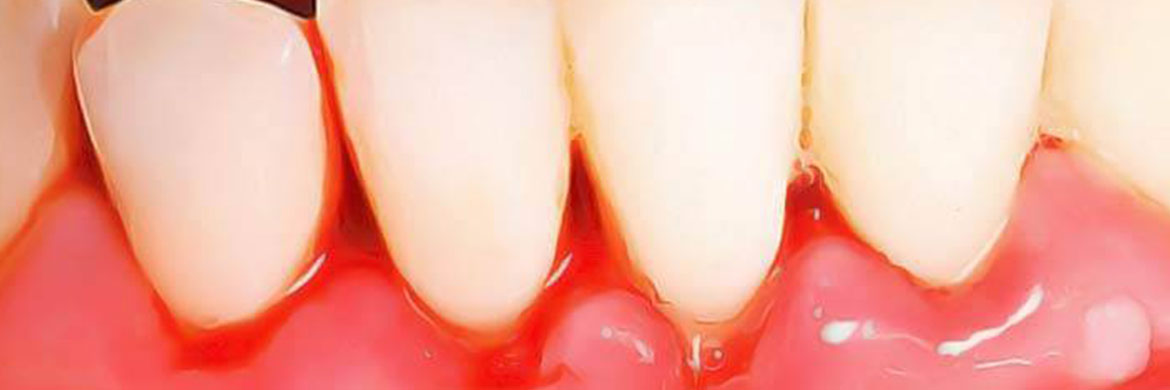

Maladies gingivales